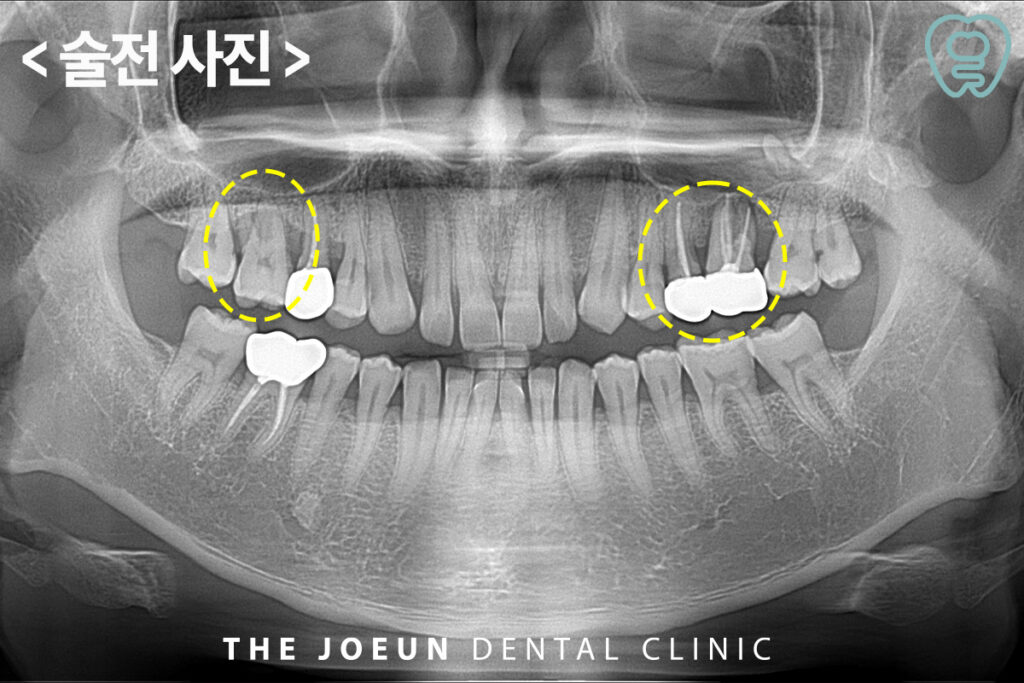

오늘은 양쪽 모두 상악동 거상술을 동반하여 발치 후 즉시 임플란트 식립을 진행하신 환자분을 소개해 드리도록 하겠습니다.

환자분께서는 양쪽 위 어금니 부위에서 냄새가 나는 것 같고 찝찝한 느낌이 드신다며 치료 상담을 위해 내원해 주셨습니다. 파노라마 촬영 후 확인해보니, 양쪽 위 어금니는 잇몸의 염증으로 인해 잇몸뼈가 이미 많이 녹아있는 상태였고 왼쪽의 경우 신경치료 후 크라운이 되어 있어 양쪽 모두 예후가 좋지 않다고 판단되어 발치 후 임플란트 식립 계획을 수립하였습니다.